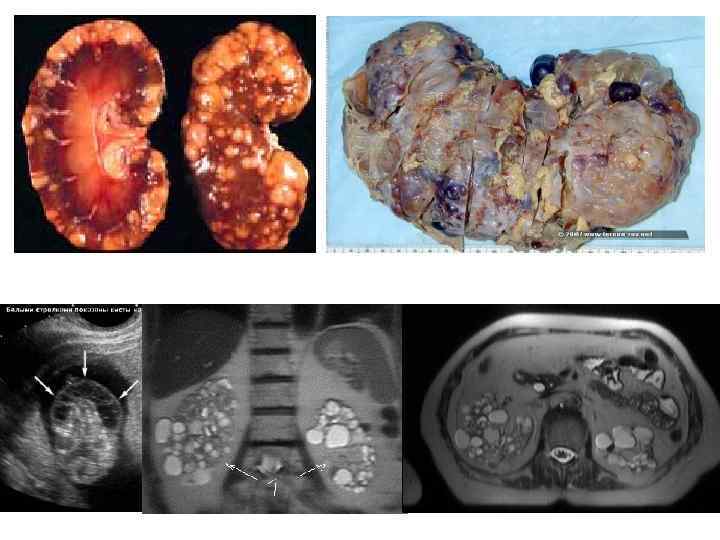

Ренопаренхиматозные артериальные гипертонии • острый и хронический гломерулонефрит и пиелонефрит • поликистоз почек • врожденный или приобретенный обструктивный гидронефроз • аномалии почек • диабетический гломерулосклероз • волчаночный нефрит • лучевое поражение почек

Ренопаренхиматозные артериальные гипертонии • острый и хронический гломерулонефрит и пиелонефрит • поликистоз почек • врожденный или приобретенный обструктивный гидронефроз • аномалии почек • диабетический гломерулосклероз • волчаночный нефрит • лучевое поражение почек